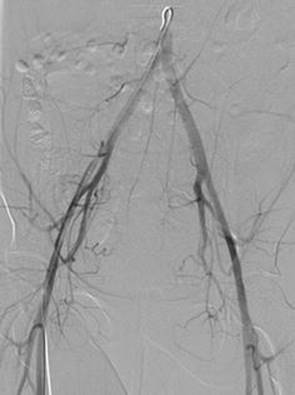

In patients in whom fertility is not desired, or for whom more conservative measures have failed, emergent endometrial ablation , uterine artery embolization (UAE) , or hysterectomy may be required. None of these methods are recommended for women desiring future fertility, and endometrial ablation is contraindicated in the setting of known or suspected uterine malignancy (and endometrial sampling beforehand is mandatory) [35]. Endometrial ablationentails the transvaginal destruction of the endometrium, performed using a variety of methods, including hysteroscopic resection, bipolar radiofrequency, microwave energy, and heat, among others [36–38]. Uterine artery embolization, performed by interventional radiology, involves the cannulation of the femoral artery followed by catheter-guided delivery of embolic particles to the uterine arteries (Fig. 2.1) [39]. UAE is used for the management of fibroids and uterine arteriovenous malformations and can be considered for the urgent management of refractory acute uterine or cervical hemorrhage due to other causes [40, 41]. Contraindications include current pregnancy or severe coagulopathy in which femoral puncture and intravascular procedure would be very high risk for bleeding. Overall, UAE is a relatively low-risk and well-tolerated procedure, though it can result in significant cramping and fevers; complications include groin puncture site infection or hematoma, contrast allergy, arterial trauma, or accidental embolization of nontarget vessels [42]. Though not recommended in women desiring future fertility, UAE may be required for severe vaginal hemorrhage that would otherwise require hysterectomy. Successful pregnancies after UAE have been reported [43].

Fig. 2.1

Uterine artery embolization . Pelvic angiogram during bilateral uterine artery embolization, performed in a 24-year-old with refractory anovulatory uterine bleeding, not adequately addressed with IV conjugated equine estrogen